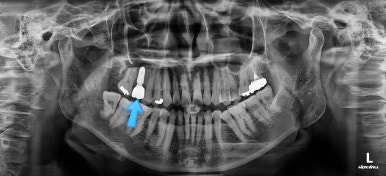

어금니를 뒤로 밀어주기 위해서 미니스크로와 브라켓, 철사를 이용해줍니다.

중간중간 장치 디자인이나 미니스크류의 위치를 바꿔주기도 합니다.

점점 자리가 확보되어가는게 보이시죠?

적절한 공간이 확보되었다고 판단되면 임플란트를 식립합니다.

임플란트가 뼈에 단단히 붙은 몇개월의 시간동안 교정치료를 좀 더 마무리 해주고요.

임플란트 머리 부분까지 완성이 되었습니다.